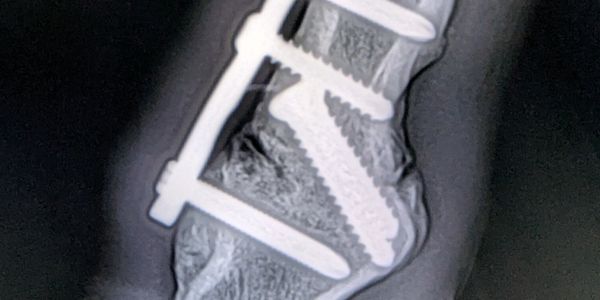

Mid-Michigan Animal Medical Center has a full line of advanced diagnostic equipment including multiple digital X-ray units, ultrasound, upper airway endoscope, and a 3.5M gastrointestinal scope.

Our digital diagnostics allow us to send images to your own vet or a board certified radiologist the same day. No need to wait days for an answer!

Mid-Michigan Animal Medical Center is proud to provide it’s clients with the latest in diagnostic technologies. From digital radiographs to diagnostic ultrasound, we can find the answer you and your horse need.

Wireless digital radiography allows for on-farm developing and viewing of radiographs for instant results and answers.